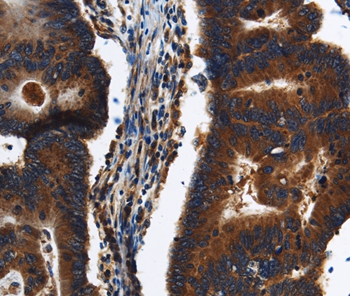

Immunohistochemical analysis of paraffin-embedded Human colon cancer tissue using #37687 at dilution 1/20.

Immunohistochemical analysis of paraffin-embedded Human liver cancer tissue using #37687 at dilution 1/20.